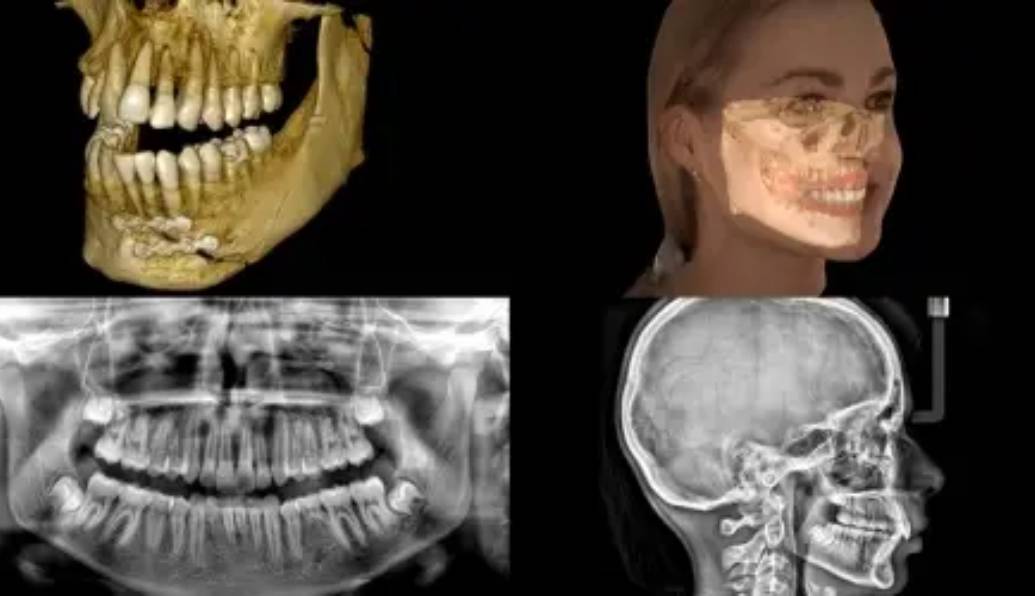

Alban City Dental & Surgical Centre is proud to be at the forefront of advanced dental care. We’re delighted to offer the state-of-the-art Carestream 9600 Cone Beam Computed Tomography (CBCT) scanner, which enables 3D facial scanning, intra-oral scanning and lateral cephalometry. This technology has revolutionised dental diagnostics, delivering unparalleled precision and clarity.

At Alban City Dental & Surgical Centre, our Carestream 9600 CBCT scanner produces high-resolution, three-dimensional images of the oral and maxillofacial region. This level of detail empowers dentists to identify issues with precision, whether it’s an impacted tooth, a cyst or a hidden infection. Accurate diagnoses lead to improved treatment outcomes, providing patients with peace of mind.

Our 3D face scanning, intra-oral scanning and lateral cephalometry capabilities provide a comprehensive view of a patient’s oral and facial structures. This wealth of information proves invaluable in planning treatments such as orthodontics, dental implants and oral surgery. The precision offered by our scans ensures that procedures are performed with the utmost accuracy, reducing the risk of complications.

The clarity of the images produced by our Carestream 9600 CBCT scanner fosters patient education and engagement. Patients can visualize their dental issues, understand the proposed treatments, and actively participate in their oral health journey. This shared understanding between patients and dentists leads to better treatment compliance and overall satisfaction.